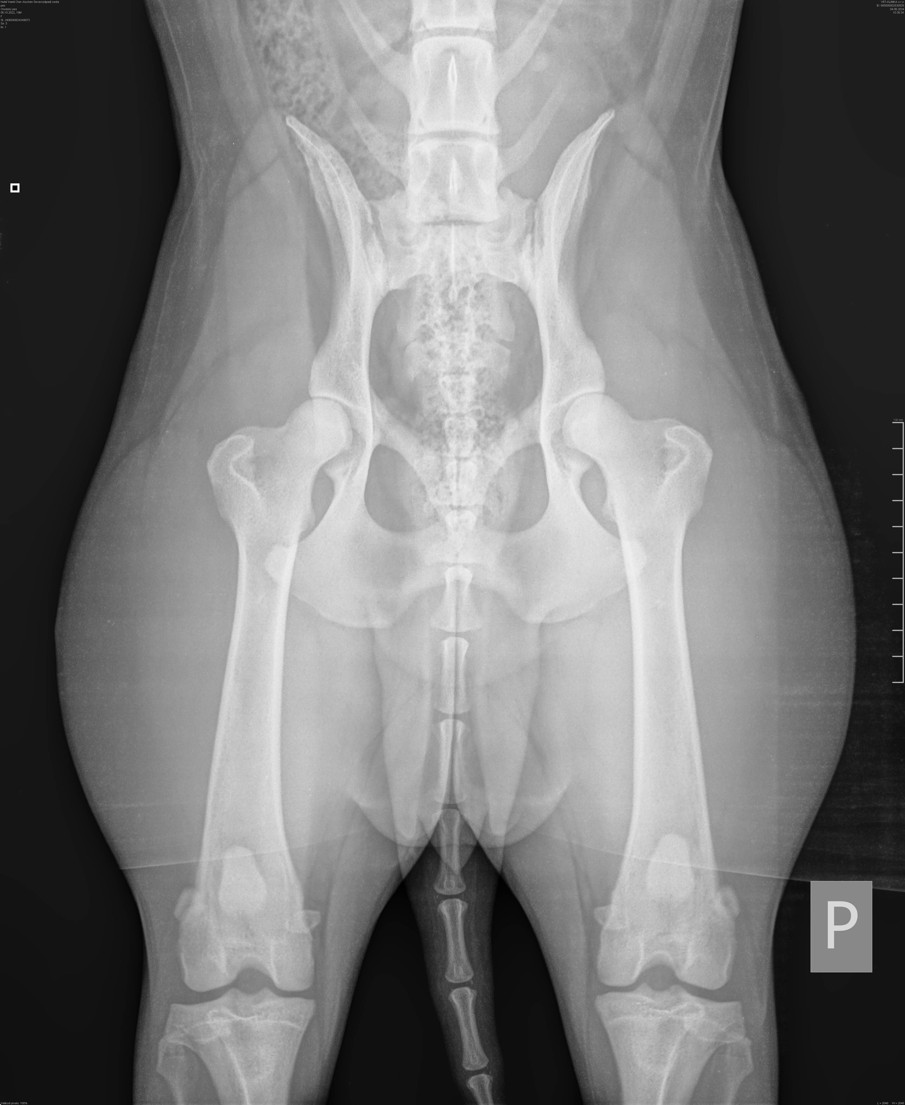

Ráda bych touto cestou připomněla všem majitelům českých horských psů, kteří absolvovali v roce 2025 bonitaci svého psa nebo feny, že je potřeba splnit všechny podmínky zařazení do chovu. V letošním roce proběhly dvě bonitace, kterých se zúčastnilo více než 20 jedinců. Téměř polovina z nich neměla vyšetření DKK (dysplazie kyčelního klou...

Jste majitelem krásného psa, nebo fenky a máte chuť udělat něco pro zachování dalších budoucích generaci našeho Českého horského psa? Co vše to obnáší a co je potřeba udělat i absolvovat: Účast na klubové, nebo speciální výstavě českého horského psa Bonitace (viz. Bonitační řád klubu ČHP) DKK (rentgen na dysplazii kyčelního kloubu) U...